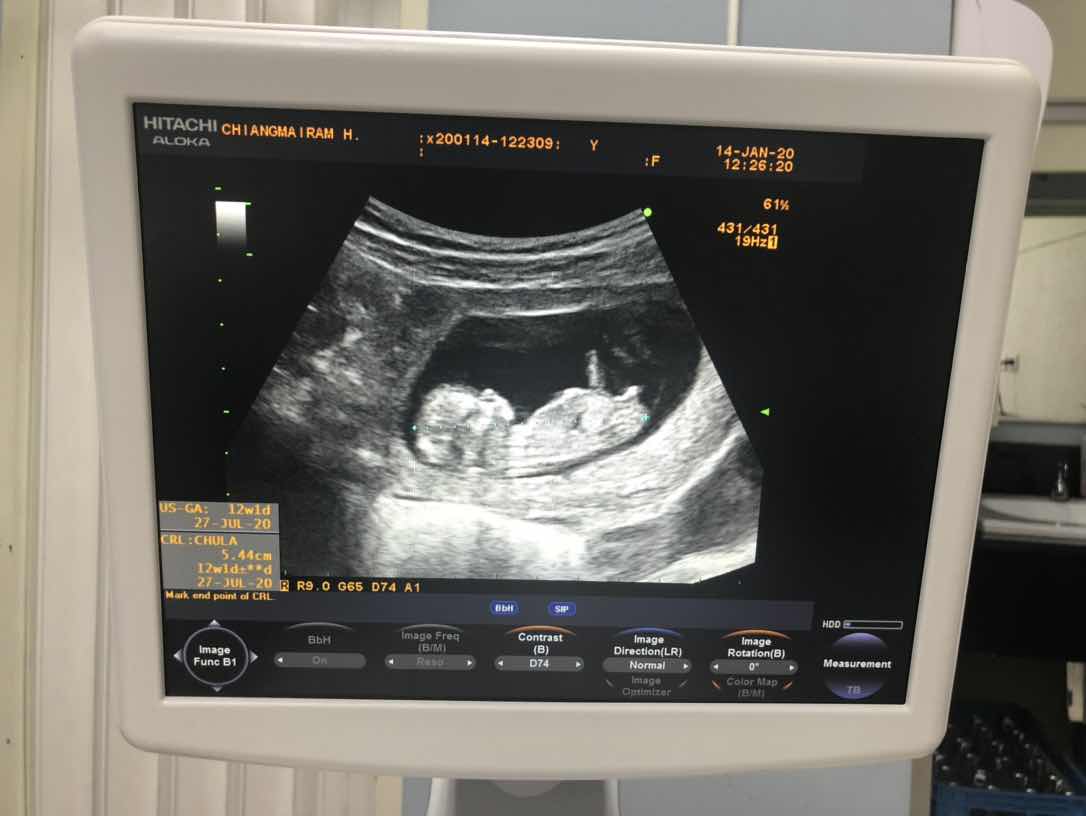

12 w จ้า

Post reply image